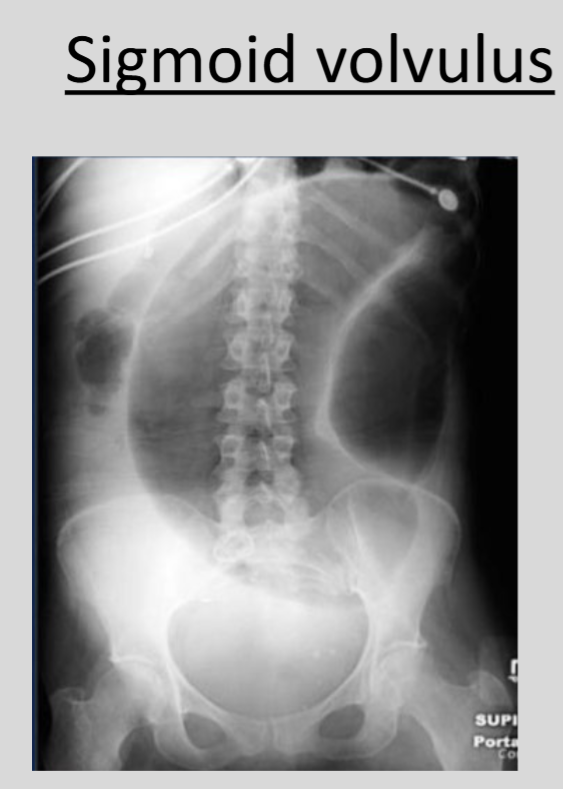

What is the significance of the 'coffee bean sign' in medical imaging?

The 'coffee bean sign' is indicative of sigmoid volvulus, a condition in which the sigmoid colon twists on itself.